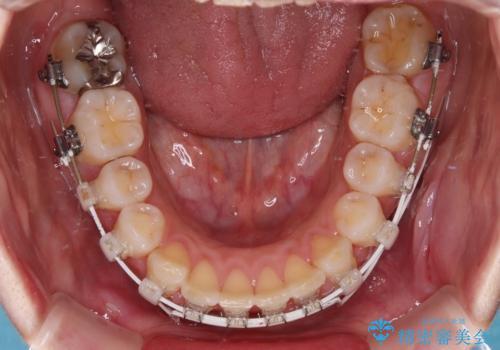

- 矯正装置

- 審美装置

- 治療計画

- 上の前歯が出っ歯と突出した口元を気にして来院された患者様です。

上顎歯列全体が前方に飛び出している印象であったので、上顎左右の第一小臼歯2本を抜歯し、ワイヤー装置にて抜歯矯正を行うこととしました。